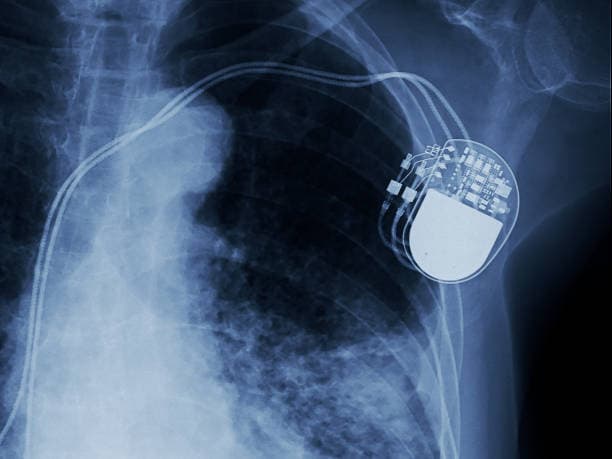

The pacemaker consists of two main components: a pulse generator and one or more leads (wires). The pulse generator is a small, battery-powered unit that produces electrical impulses. It is typically implanted under the skin, just below the collarbone. The leads are thin, flexible wires that extend from the pulse generator to the heart. These leads are threaded through blood vessels and attached to the heart muscle. They transmit the electrical impulses from the pulse generator to the heart, stimulating it to contract at a regular rate.

Modern pacemakers are sophisticated devices that can be programmed to meet the specific needs of each patient. They come in various types, including single-chamber, dual-chamber, and biventricular pacemakers. Single-chamber pacemakers have one lead that is usually placed in the right ventricle, while dual-chamber pacemakers have two leads placed in the right atrium and right ventricle, allowing for coordinated pacing of both chambers. Biventricular pacemakers, also known as cardiac resynchronization therapy (CRT) devices, have three leads placed in the right atrium, right ventricle, and left ventricle, and are used to improve the heart's efficiency in patients with heart failure.

The implantation of a pacemaker is a minimally invasive procedure performed under local anesthesia. The surgeon makes a small incision near the collarbone and threads the leads through a vein to the heart. The pulse generator is then implanted under the skin, and the leads are connected to it. The entire procedure typically takes a few hours, and most patients can return home the same day or the next.